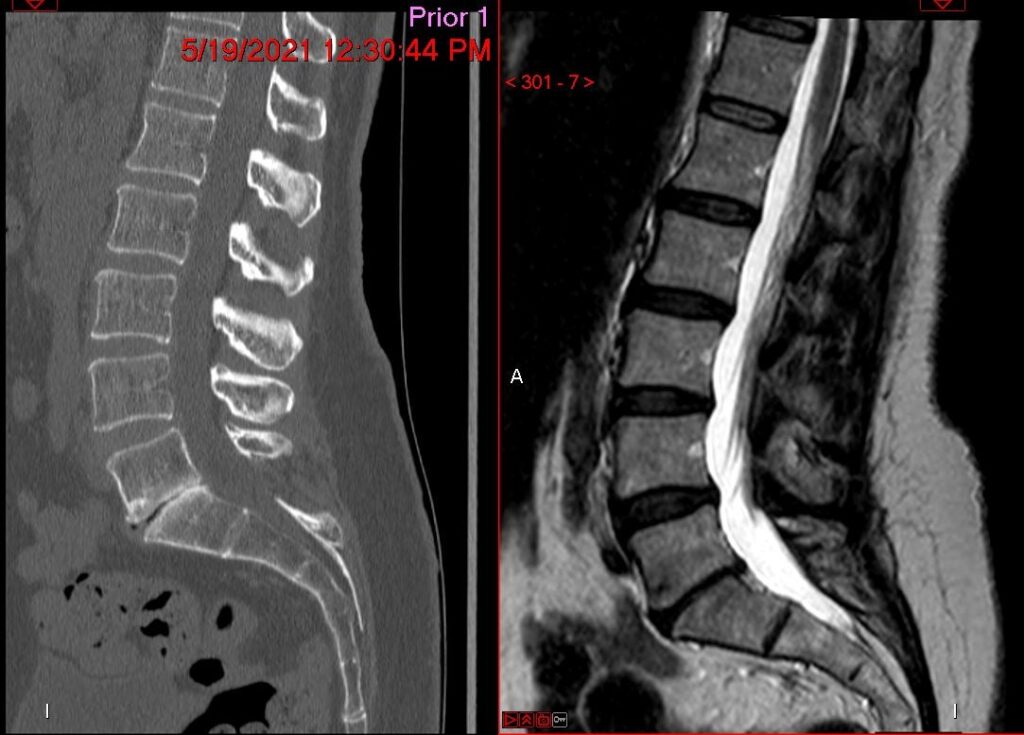

Anterior Lumbar Interbody Fusion